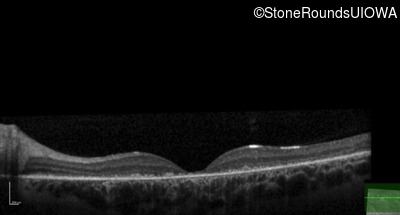

Age at visit: 15 years

OD OS

Age at visit: 16 years

Age at visit: 19 years

Age at visit: 23 years